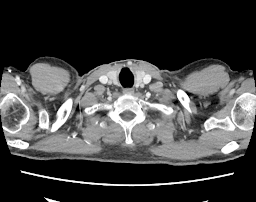

Een beetje vertraging omdat ik geen CD-ROM meer heb thuis… maar hier zijn dan eindelijk de beelden van mijn eerste scan-check. […]